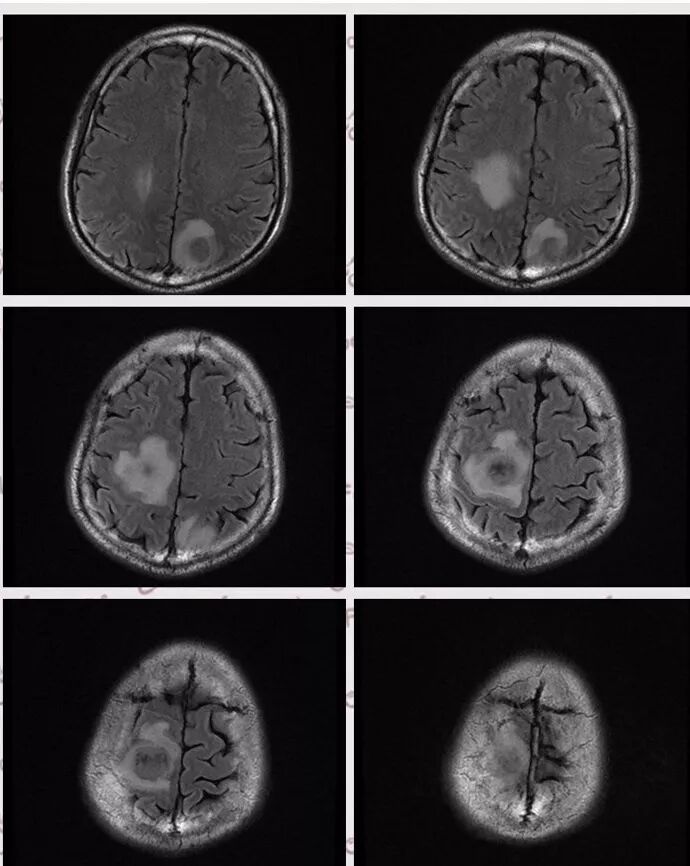

右肺下叶团块状密度增高影,边缘模糊,其内见液性低密度影,多发小气泡影及充气支气管征,考虑肺脓肿。颅内双侧顶叶长T2长T2病灶,周围水肿,DWI高信号,增强扫描囊壁环形强化,囊壁钙化,周围水肿,考虑脑脓肿。患者长期接触垃圾,什么菌都有,肺、脑脓肿,考虑肺克。再有肝脓肿就更支持了。

右肺下叶背段实变,广基底,糊墙,长轴与平行胸膜,周围有晕,支气管进入堵塞,可见低密度坏死及小空泡。颅内多发环形强化灶,符合脑脓肿三层结构,结合临床,考虑:感染性病变,隐球菌?鉴别肺克。

颅内多发类圆形等或长T1长T2信号,周围见少量环形水肿带,考虑多发脓肿,不符合转移瘤表现。综合肺脑脓肿,考虑隐球菌可能

右肺下叶见不规则软组织影,边缘不清,内夹杂气体,背段支气管未见明显阻断,增强扫描下叶病灶内见类圆形低强化区,其边缘光滑,见低强化区壁,颅脑左侧枕叶及双侧顶叶见多发长T1长T2信号,T2高信号内见类圆形异常信号,壁呈低信号,DWI环形壁未弥散受限,内容物弥散受限,周围为水肿区,增强扫描呈多发环形强化,考虑血源型感染,颅内及右肺下叶脓肿形成

脑内右侧顶叶病灶与其它脑内病灶不一致,壁弥散受限,内容物弥散低信号,转移瘤不能排除,其它脑内病灶支持脑脓肿

肺内病灶符合脓肿,颅内病灶几个表现不一样,多数脓腔弥散受限,壁不受限制,但有一个表现跟其他不同,内部不受限,壁弥散受限

多数薄壁,脓腔弥散受限是典型脑脓肿;右侧额叶的厚壁,壁受限,表现跟其他完全不一样,很是疑惑

颅内部分病灶是环形受限,中心没有受限,不支持脓肿

脑部病灶DWI受限,脓肿,中间也有受限,DWI第一,第二张图都是中间受限,第三,四是周围受限

今天这个颅脑病灶需要转移和脓肿鉴别,转移和脓肿都可以这样环形强化,但是脓肿是中心弥散受限,脓肿壁弥散不受限,转移和脓肿弥散正好相反,转移是环壁弥散受限,中心坏死区弥散不受限。

DWI值对鉴别脑脓肿与囊性脑转移瘤有重要意义。包膜期脑脓肿其内容物主要为炎症细胞、微生物及蛋白质,其黏稠度相对较高,水分子弥散受到限制,DWI表现为均匀高信号。转移瘤囊变区主要以浆液性坏死物为主,其黏稠度相对较低,水分子扩散速度相对较快,DWI表现为低信号

脑脓肿和囊性脑转移瘤的鉴别点就是粘液(结合水)浆液(自由水)的鉴别

下图是例举其他病例:

脑内多发结节,DWI壁弥散受限,腔不受限

颅内环形的高信号,但是可以发现这个的DWI环是厚的,但是增强扫描的环是非常薄的,如果是肿瘤的,就是壁的弥散受限是肿瘤细胞的话,那么他强化的环应该跟DWI的环的厚度是一样的,所以这个环形的低DWI高信号应该是脓肿。而且就是关于这个脓腔壁的,就是脓腔的外壁是非常模糊的,而内壁还是相对光整,环不是很完整。下面一个图,没有给到,DWI上可以看到沿着破溃的脓肿壁向外侵出去的感觉,如果是环形转移的,那么它的那个内壁是更加不光整,而外壁是相对比较清楚一些的。

这个颅内病灶增强扫描的无强化区范围与DWI高信号范围是一致的,所以还是脓腔内受限,至少时期不那么典型,不是纯粹的高信号,DWI是厚层、增强是薄层;而且扫描角度也不一样,所以无法完全对上

脓肿内的坏死、脓液形成也不是一次性完全形成的,就像在肝脓肿内,信号也是不一致的。重点还是在于强化区的地方弥散受限了还是无强化区的地方受限了,还是那句话,强化壁比弥散壁薄很多,无强化区比弥散不受限区范围大多了

3.脑内多发混杂信号病灶,显著长T1、显著长T2信号为主。注意TW1及TW2均显示环形等密度影(这在转移瘤是非常罕见的)且出现相应的环形强化。中央液化区DW扩散受限以及周边广泛水肿等,都符合典型多发脑脓肿改变。

4.脓腔较大,也更符合细菌感染。(脑内结核、隐球菌及奴卡菌感染病灶通常不易有如此大范围)

综上患者符合肺脓肿及脑脓肿诊断,病原菌以肺炎克雷伯杆菌等感染可能性较大